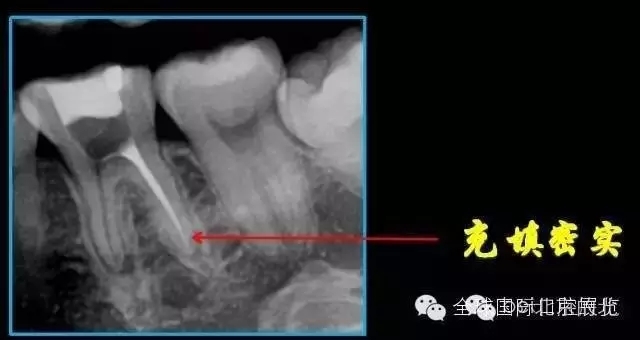

終于完成根充

MM,ML其實(shí)融合為一個(gè)根管口的,截面就是三根管的形態(tài),然后做了一個(gè)簡(jiǎn)單清晰的三維重建,形態(tài)還是挺不錯(cuò)的 。